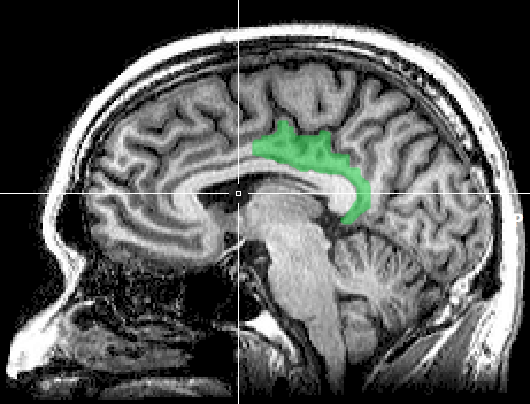

MRI anterior cingulate

Scientists have discovered that if you let someone’s mind wander while scanning their brain, you see a constellation of brain areas that become active together. There are three brain areas that form the core of this network. One is the medial prefrontal cortex, a region of the part of the brain behind your forehead that we met earlier. Instead of sitting on the surface directly under the skull, however, it sits on the side of the brain where the two hemispheres meet, in the same way as the cingulate cortex that we also met earlier. The posterior cingulate cortex, located behind the anterior cingulate cortex, is another key area of this network. Finally there is the angular gyrus, a bump of brain tissue that sits just above your ears. This network is active when you’re in your everyday, default way of being. As a result, it is known as the default mode network (DMN).

MRI of posterior cingulate